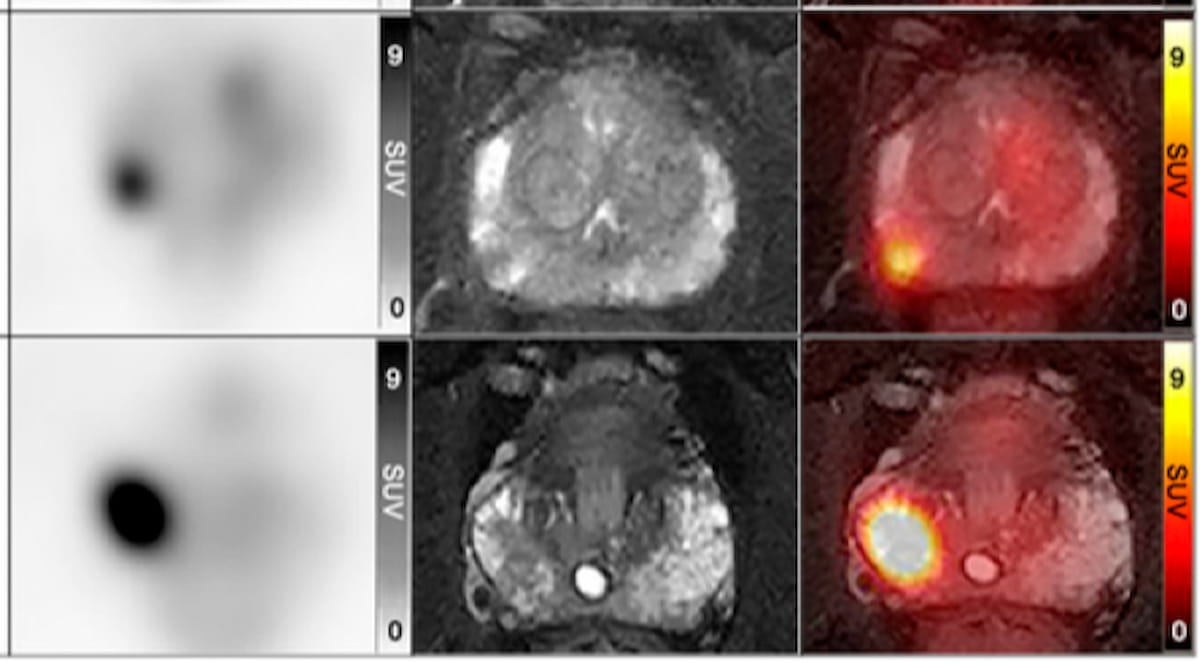

Sixty-five percent of patients with newly diagnosed high-risk prostate cancer may have extraprostatic extension on MRI, and PSMA PET/CT findings suggest those with Gleason scores of eight or higher have more than double the risk of metastasis, according to a new study presented at the European Congress of Radiology (ECR).